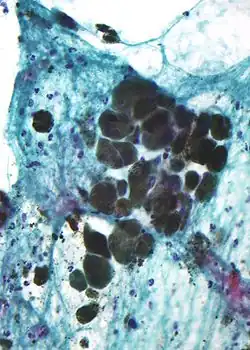

Melanin is brown, non-refractile, and finely granular with individual granules having a diameter of less than 800 nanometers. This differentiates melanin from common blood breakdown pigments, which are larger, chunky, and refractile, and range in color from green to yellow or red-brown. In heavily pigmented lesions, dense aggregates of melanin can obscure histologic detail. A dilute solution of potassium permanganate is an effective melanin bleach.[53]